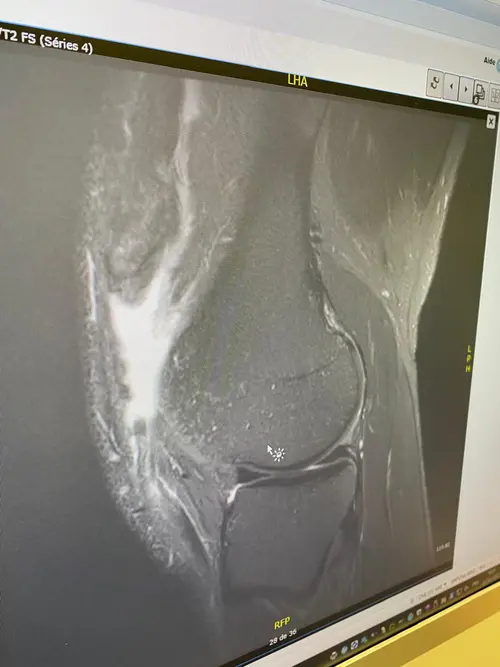

I can still remember the sound — that sharp pop as I went up to dunk the ball. Everything changed in an instant. I had torn my patella tendon. In that moment, my world froze. The pain hit hard, but what hit harder was the thought that my career might be over. Everything I had worked for flashed before my eyes.

The surgery was special — done by the former Chelsea Football Club doctor. He used a unique technique on my knee, something that gave me a spark of hope. From there, I dedicated myself to recovery like it was my full-time job. For six straight months, I did everything my physios and doctors told me to do. No shortcuts, no excuses. Every stretch, every rep, every painful step forward — I did it with purpose. I worked so hard, they literally made me go home for staying at the rehab center too long!

Then November 2021 hit — and so did the other knee. Another patella tendon gone. Same pain, same shock. But this time, the doctor’s words cut deeper than the injury itself. He looked at me and said I’d never run or walk normally again, let alone play basketball. He even laughed and said it must be genetic — that I’d never be the same.

At first, they misdiagnosed it as a knee sprain. I walked around on a torn patella for two months before getting the right diagnosis. By then, my patella was just 1.3 mm from the bone — they couldn’t fix it and had to build a new one using part of my hamstring. Still, my faith in God made me believe everything would be alright if I kept my strength and faith strong.